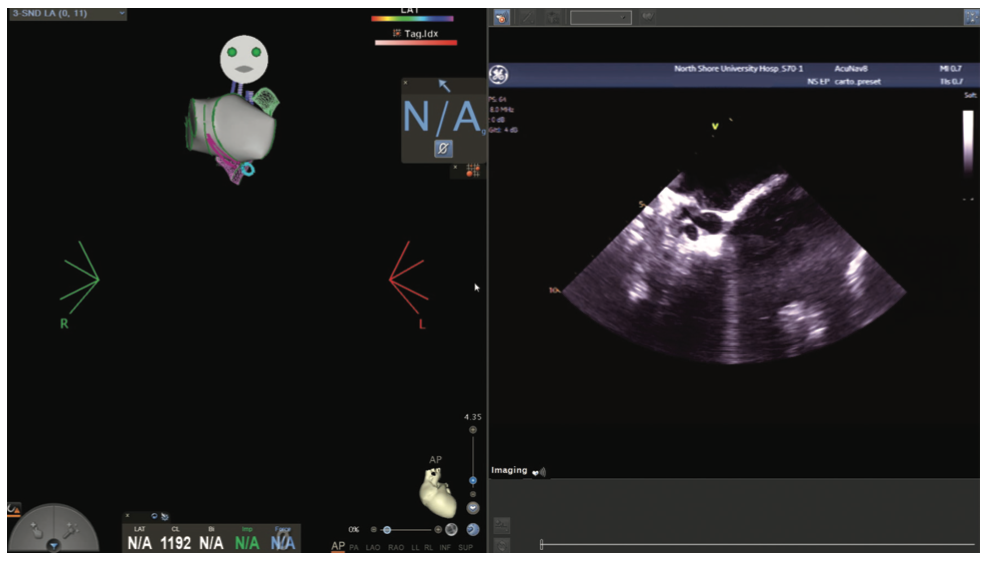

Even with an EAM system, however, the need for fluoroscopy was critical to safely obtain access to the left side of the heart via either transseptal access or retrograde aortic cannulation. The initial availability of radial/rotational intracardiac echocardiography (ICE) in 1999, followed by phased array ICE in 2002, eventually helped to overcome concerns about safe transseptal or retrograde access.4

Figures/Videos 1-10 demonstrate the process of navigation from groin access to the heart to create biatrial geometry, localize the esophagus, and gain transseptal access. Many currently practicing electrophysiologists use very little fluoroscopy to map and ablate the left atrium (LA) with the current multielectrode catheters and EAM systems once transseptal access is obtained.

The videos and figures included here should be beneficial in helping to reduce or eliminate fluoroscopy during complex ablations. It is important to note that there is a learning curve and one should not hesitate to use fluoroscopy to safely and effectively perform procedures based on the operator’s comfort. Despite the sophisticated mapping and ablation tools currently available, one should not base ablation strategy primarily on color maps, but rather on a thorough understanding of the electrograms, sampling windows, and conduction properties from which they are derived. The additional use of ICE for anatomic confirmation further enhances efficacy and safety.